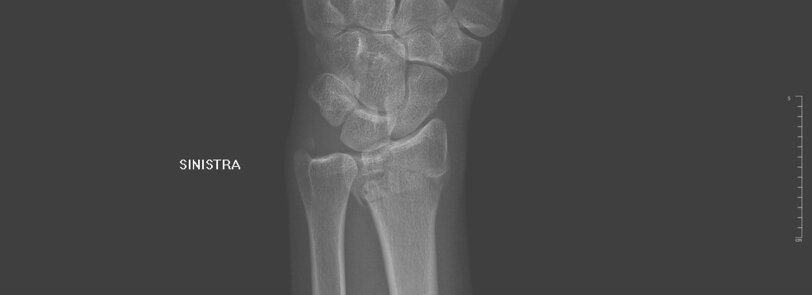

L'indagine diagnostica principale per poter eseguire la diagnosi è la radiografia del polso, ma in alcuni casi, possono esser necessari degli approfondimenti TC.

Le fratture di polso sono definite come le fratture dell'epifisi distale del radio e/o dell'ulna.

Rappresentano il 17.5% di tutte le fratture, con un'incidenza maggiore nel sesso femminile (3:1). Hanno una distribuzione bimodale: nei giovani sono causate da traumi ad alta energia, negli anziani da traumi a bassa energia.

• Fratture di Colles: fratture extra-articolari con frammento distale dislocato dorsalmente;

• Fratture di Smith: fratture extra-articolari con frammento distale dislocato ventralmente;

• Frattura dello Chauffer: frattura della stiloide radiale;

• Frattura di Barton: frattura intra-articolare con dislocazione volare o dorsale del carpo.